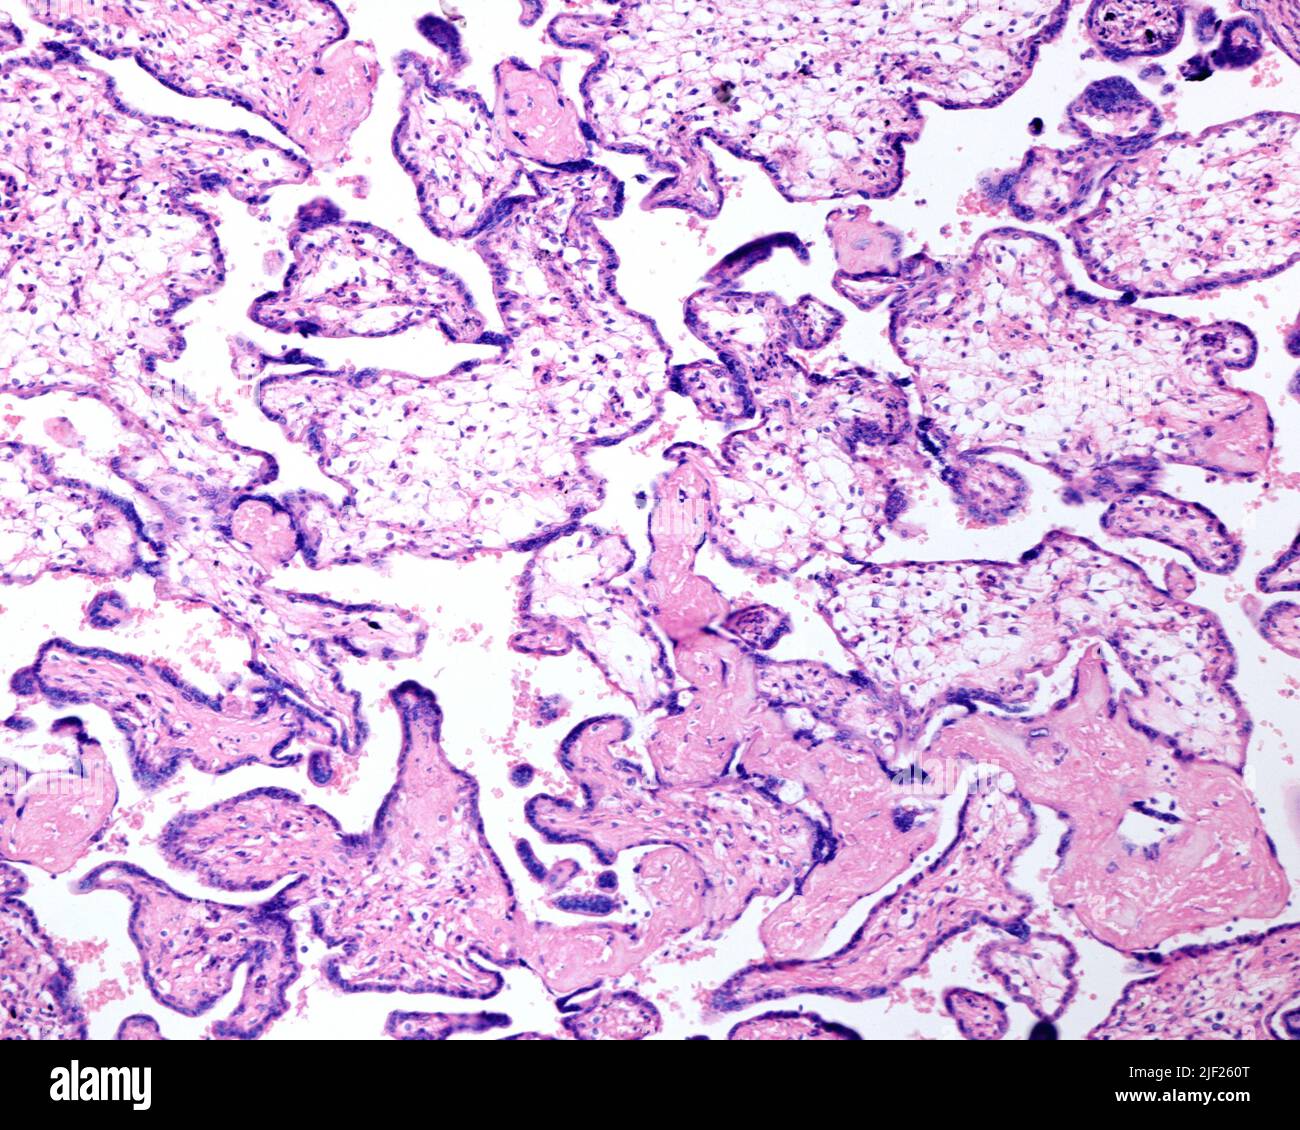

Si chiama "eritroblastosi fetale" in quanto, per fare fronte alla grave anemia, il midollo osseo del feto immette in circolo anche i precursori immaturi degli eritrociti, gli eritroblasti.

L'ingresso di cellule ematiche fetali nel sistema circolatorio materno causa una risposta immunitaria da parte della madre, con formazione di anticorpi anti-D. Nel caso in cui la donna abbia una seconda gravidanza con feto Rh positivo, gli anticorpi anti-D materni entreranno nel circolo fetale già a partire dal 4º mese: infatti, essendo già avvenuta una risposta primaria sono sufficienti anche minima quantità di sangue per scatenare la risposta immunitaria. Gli anticorpi anti-D riconosceranno gli eritrociti fetali come estranei, distruggendoli causando un'anemia emolitica.

- Anemia di tipo emolitico, con un'elevata produzione dei globuli rossi come meccanismo di compenso;